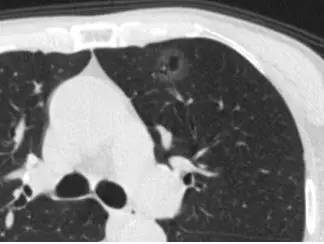

1. 空泡型 GGO

这个也像 GGO,还有一个小空洞